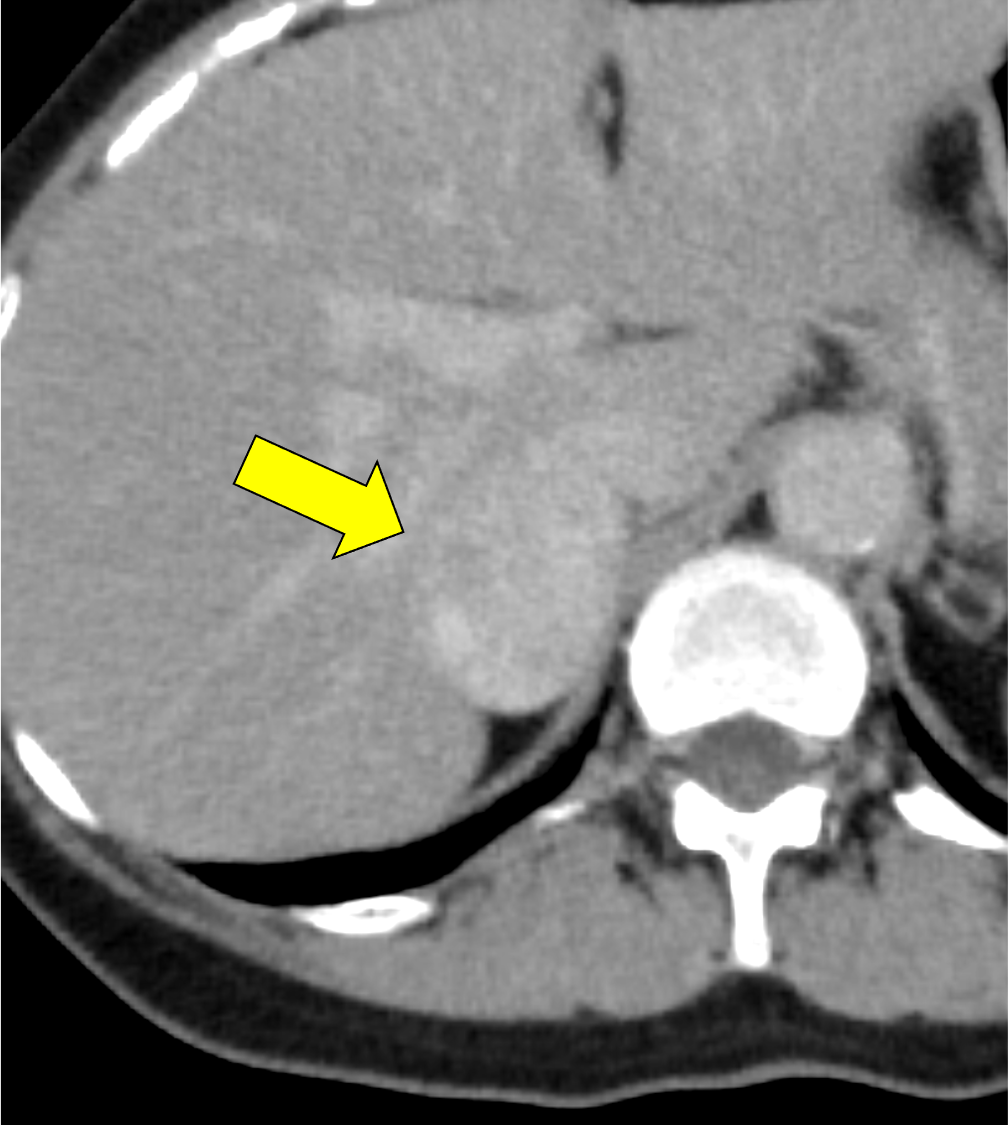

褐色細胞腫は副腎髄質に存在するクロム親和性細胞に由来する腫瘍で、カテコールアミンなど種々の生理活性物質を産生する。ダイナミック造影で動脈相での強い濃染と持続する造影効果が特徴とされ、サイズが大きい病変は嚢胞変性や出血、壊死を伴うことが多い。かつては、臨床的に褐色細胞腫が疑われる場合、ヨード造影剤の投与はカテコールアミンの過剰放出を誘発し、高血圧クリーゼを引き起こす可能性があるため原則禁忌とされていた。しかし、現在汎用されている非イオン性・低浸透圧性造影剤であればこの現象は起こらないとの報告もあり、European Society of Urogenital Radiology Guidelines on Contrast Media, ver 10.0では、「経静脈的ヨード造影剤の投与をする場合でも特別な準備の必要はない」と記載されている。イオプロミドの電子添文上は、禁忌にはなっていないものの、「慎重に投与すること」との記載になっている。本例では、血管腫疑いとして合計5回の造影CTが行われているが、血圧変動や頭痛、動悸などの症状は一度も認められなかった。

本例の画像所見として、褐色細胞腫としてダイナミック造影の濃染パターンは典型的ともいえたが、大きさの割に変性が乏しい点、MIBGシンチでの核種集積に乏しい点、ホルモン産生に乏しい点など非典型的な要素が複数存在し、海綿状血管腫を除外しきれなかった。なお、褐色細胞腫はRET遺伝子変異による多発性内分泌腺腫症(multiple endocrine neoplasia;MEN)type 2A・2B、VHL遺伝子によるvon Hippel-Lindau病、NF1遺伝子による神経線維腫症1型に生じることが知られているが、これらの疾患を想起させるような他病変は本例には見つかっていない。

腺腫や骨髄脂肪腫など良性と断定できない副腎腫瘍の鑑別をする際、大きい病変であれば褐色細胞腫や副腎癌、悪性リンパ腫などが考慮される。核医学検査も有用ではあるが、本例のように偽陰性となることも稀にあり、その際はダイナミック造影パターン、血管への浸潤、転移の有無などから判断しなければならない。適切なタイミングで撮像されたダイナミック造影CTは、多血性病変であるかの評価、周囲の血管との関係性、多血性の転移巣の有無などの判断に寄与し、診断の重要な手がかりとなると考える。